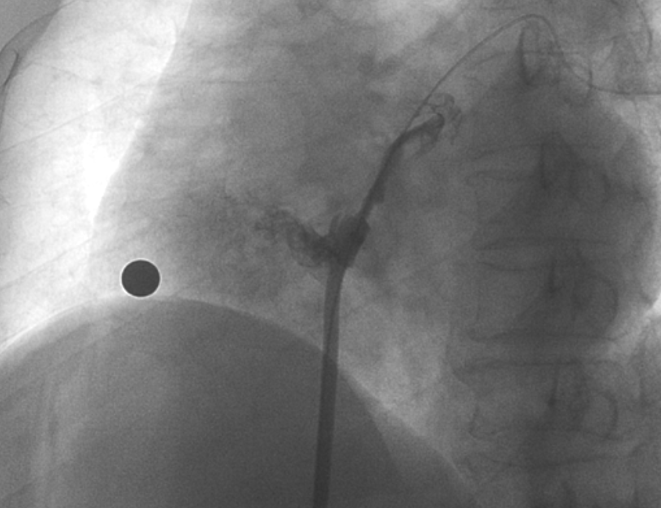

儲慧民教授團隊為患者進行經(jīng)皮卵圓孔未閉封堵術

在本次植入手術中,接受介入封堵術的是一名卵圓孔未閉(長隧道型)的患者。患者60歲,男性,7年前曾診斷腦梗死,此次因新發(fā)腦梗死入院,無房顫及頸動脈狹窄;經(jīng)胸心臟超聲和心臟聲學造影檢查提示卵圓孔未閉,Valsalva動作后心房水平大量右向左分流。經(jīng)儲慧民教授團隊評估,結(jié)合相關病史并考慮PFO及不明原因卒中,遂決定對患者開展經(jīng)皮PFO封堵術。

術中造影顯示患者為PFO且長隧道型,目前市場上已商業(yè)化的PFO封堵器難以滿足該患者解剖結(jié)構封堵需求。迪創(chuàng)醫(yī)療自主研發(fā)的OmniSeal PFO封堵器自適應性雙盤貼合設計能廣泛適應不同PFO隧道長度的解剖結(jié)構和形態(tài),其雙盤外包覆式阻流和隧道內(nèi)填充阻流相結(jié)合的雙重阻流設計,可為此患者實現(xiàn)有效封堵。與此同時,OmniSeal首創(chuàng)的完全可穿刺式設計,也為此患者最大程度地保留了房間隔區(qū)域穿刺通道,以實現(xiàn)全兼容未來可能的左心系統(tǒng)二次介入術。術終造影和心臟超聲顯示封堵完全、效果良好。作為OmniSeal的首例臨床應用,本次手術的順利完成和優(yōu)異效果充分體現(xiàn)了產(chǎn)品的設計創(chuàng)新優(yōu)勢。

造影顯示長隧道型PFO